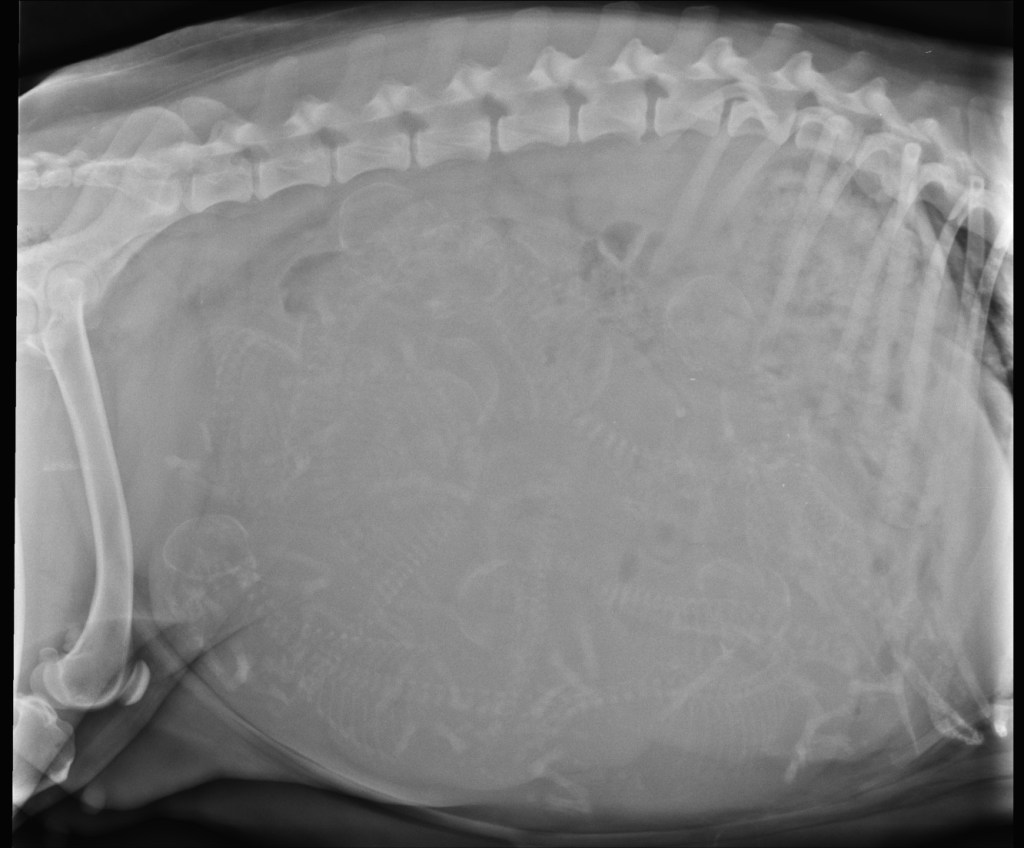

Ze is op het laatst tonnetjes-rond en kan ook niet meer mee naar het bos. Ze wil het ook niet meer. Op 19 februari maakt Douwe nog een röntgenfoto om te kijken hoeveel pups er werkelijk in zitten. Het is een drukke boel daar binnen en moeilijk te tellen. Alle assistentes komen mee helpen tellen en we komen uit op 9 pups. Alles wordt thuis in gereedheid gebracht en dan is het wachten op de eerste signalen dat de bevalling aanstaande is. We temperaturen haar gedurende een week al meerdere keren per dag. Haar temperatuur is redelijk laag voor een hond, tussen 37,7°C en 38,2°C. De temperatuurdaling die er op duidt de bevalling er aan komt missen we.